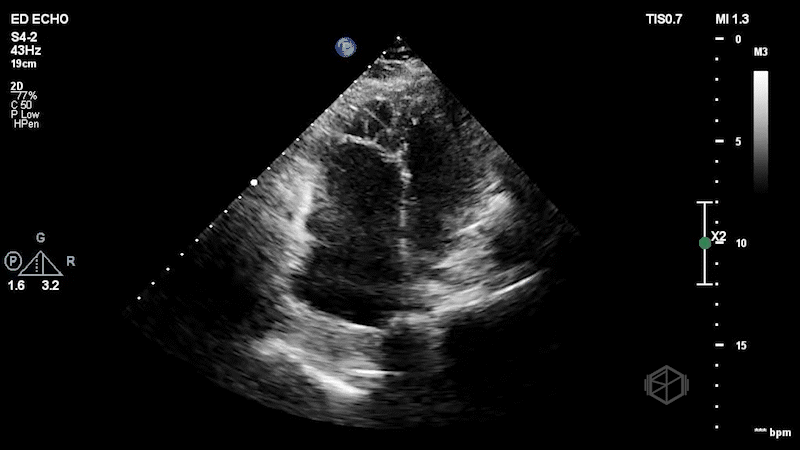

The second SonoProps goes to Dr. Hardeep Singh. Dr. Singh is rotating at Suffolk, demonstrating how POCUS makes a difference in early diagnoses. Dr. Singh evaluated a mid-60-year-old female who presented to the ED with shortness of breath and hypoxia. With multiple differentials to consider, he quickly performed a POCUS that made his diagnosis. The echo clips are shown below:

The patient has a dilated right ventricle obvious even in the parasternal long. The parasternal short view demonstrates a dilated right ventricle with a D-sign that is mostly persistent indicating RV pressure overload. The apical 4 view demonstrates apical hyperkinesis with lateral wall hypokinesis (McConnell’s sign), and the IVC is plethoric with minimal respiratory variation. Dr. Singh previously got a SonoProps for this diagnosis.

The expedited CTPE was read as “large filling defect is present in the distal left main pulmonary artery with extension into the left upper lobe branches as well as arterial branches of the left lower lobe. Filling defect is also seen within the right lower lobe pulmonary artery just distal to the bifurcation. Filling defects are present within multiple segmental branches of the right lower lobe and the right middle lobe. Filling defects are also visualized within the right upper lobe branches. There is no evidence of right ventricular strain.” Clearly, there was evidence of right ventricular strain on echo. The patient was taken for a thrombectomy.

Diagnosis: Massive pulmonary embolism with right heart strain